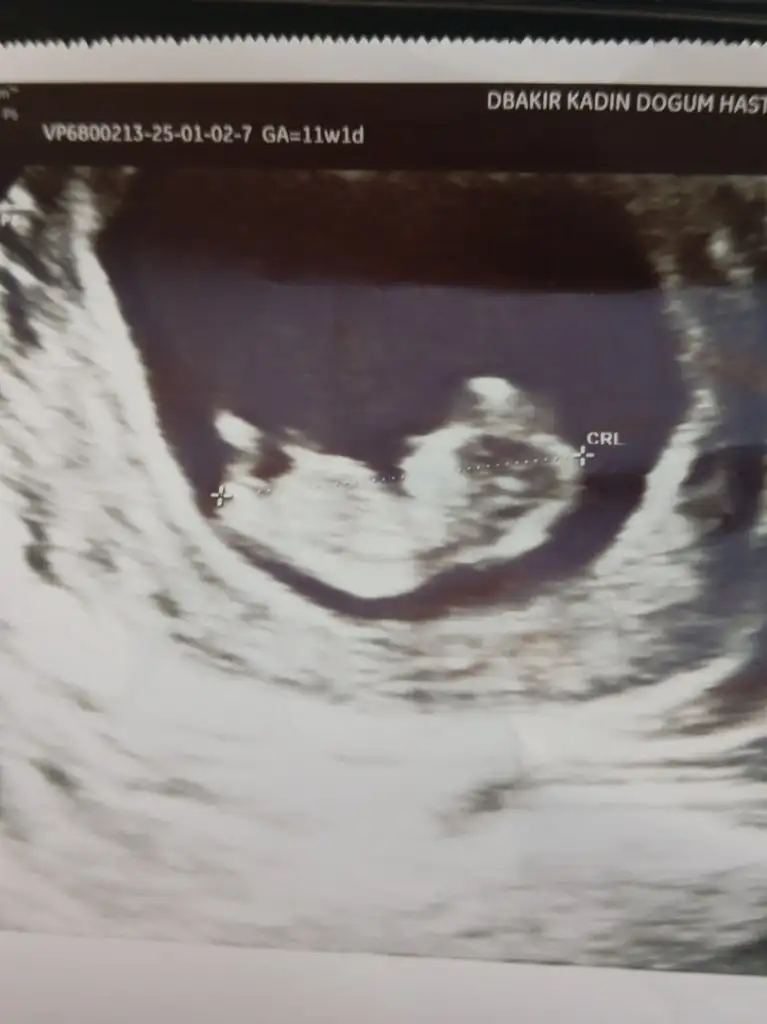

Merhaba 11 haftalık cinsiyet tahmini alabilir miyim acaba?

Bu çok küçük parlaklık ve kese sağınızdaysa erkek solunuzdaysa kızınız olcak :)